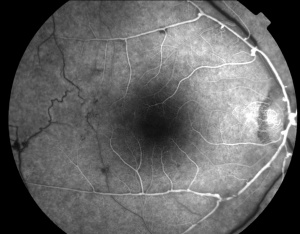

Retinal vascular sheathing may occur, but it is not a prominent feature of the disorder in most patients. In the retinal periphery, there is a variable amount of retinal nonperfusion, with obliteration of the arteries, veins, and retinal capillaries. In the perfused area bordering the peripheral areas of nonperfusion, the retinal veins may show abnormal caliber alterations. If the ischemic load of the nonperfused retina reaches a critical level, retinal and iris neovascularization may develop. Interestingly , neo-vessels may sometimes reproduce arterial macroaneurysms seen in the retinal vasculature ( Richard F Spaide MD, personal communication ). In severely affected individuals, vitreous hemorrhage and neovascular glaucoma have developed.[13]

Fluorescein angiography highlights the arteriolar abnormalities. The aneurysms are more evident and the alterations in arteriolar caliber are more obvious. Leakage of fluorescein from the aneurysms is apparent. Patients with IRVAN usually have optic nerve head staining. Of course, disc and/or retinal neovascularization show marked fluorescein leakage. The areas of peripheral non- perfusion are easier to appreciate with fluorescein angiography, especially wide-field fluorescein angiography.[23][24]